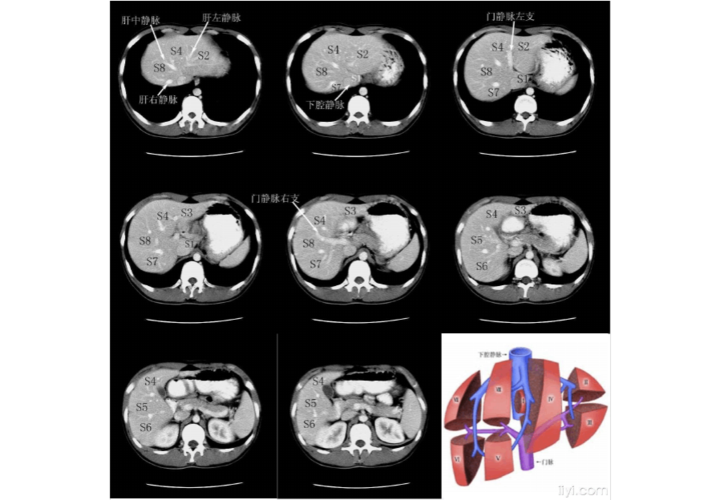

肝脏分叶分段的影像学解剖

肝脏分段ct断面解剖图

肝脏分段8段CT

CT肝脏分段

肝脏分段ct图